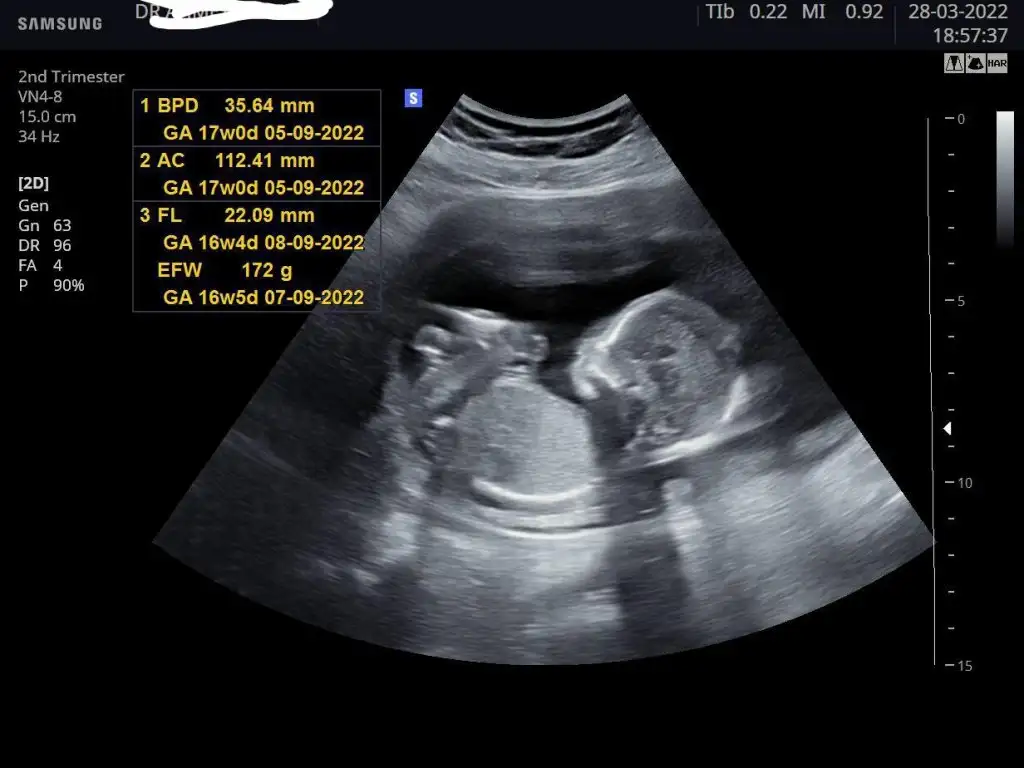

Kızlar dün geçmeyen sancıyla acile koştum. İdrar yolu enfeksiyonu dediler, ağrı öyle siddetliydi ki kendi doktoruma da gitmek istedim. Bebek de her şey yolunda çok şükür, hatta yine uyumuyor , tekme atiyordu bu kez. Detaylı ultrason randevumu da aldım gitmişken, bu arada yüzde 90 kızım oluyor 👧🏻💗